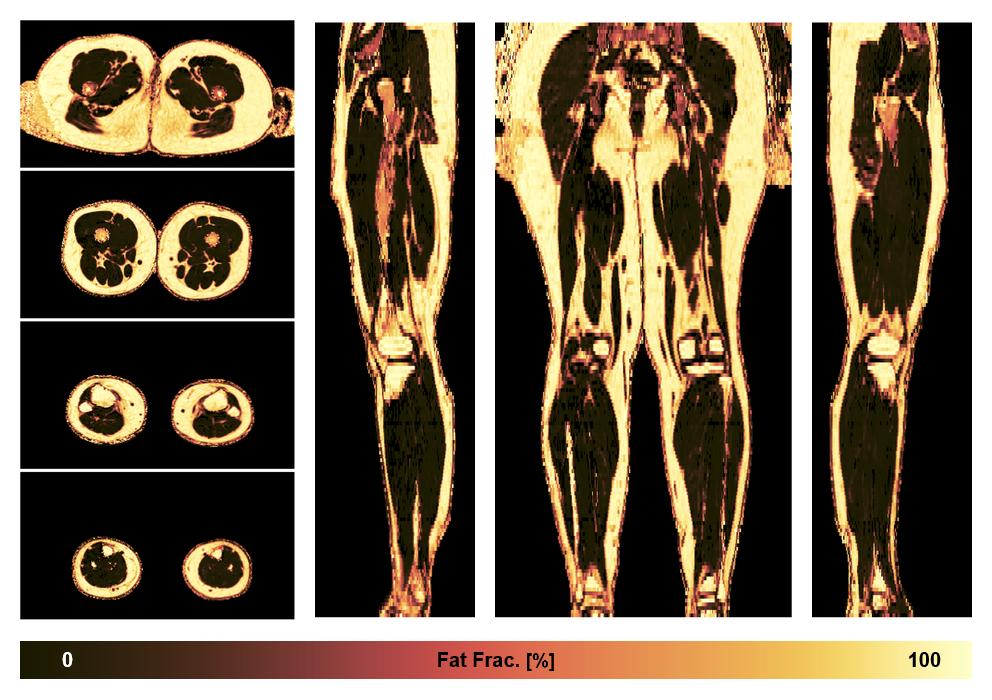

• Fat fraction

The fat fraction of the lower extremity obtained from the dixon reconstruction for muscle water fat quantification.